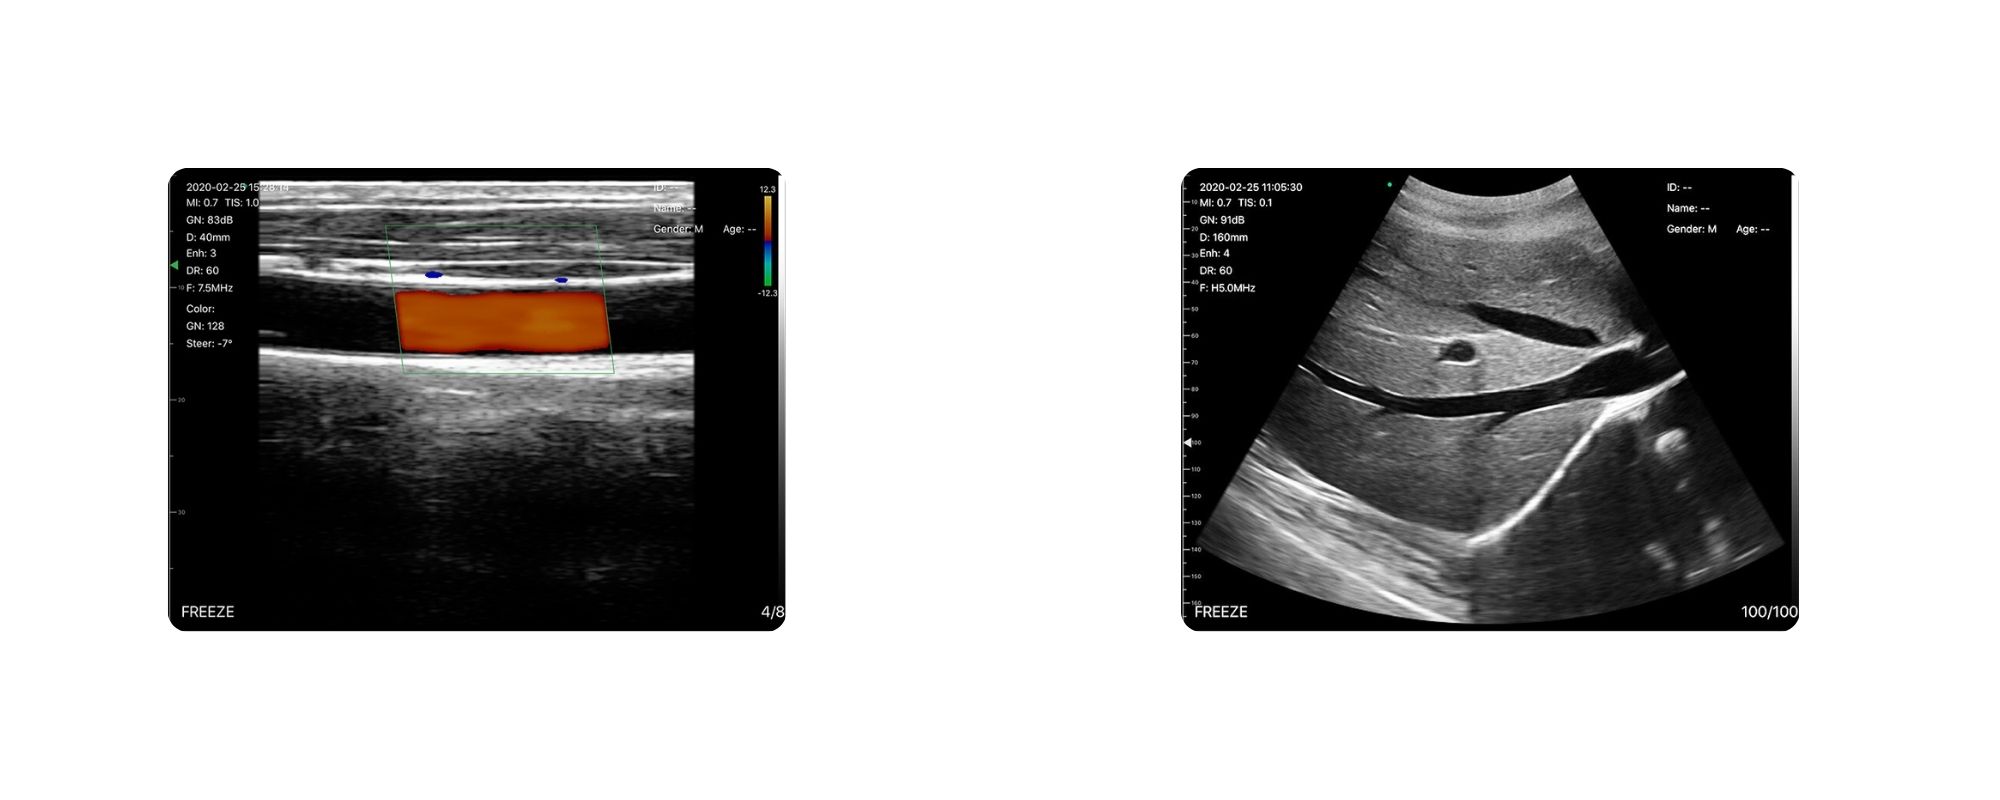

پشتیبانی از تمام مدهای تصویربرداری حرفهای

این پروب تقریباً تمامی مدهای تصویربرداری مورد نیاز در پزشکی را پشتیبانی میکند:

- B Mode – تصویر سیاه و سفید

- B/M Mode – بررسی حرکت و خطوط

- Color Doppler – نمایش جریان خون

- Pulse Wave Doppler – شنیدن صدای جریان یا صدای قلب جنین

- PDI – داپلر قدرت برای عروق ریز

این مجموعه کامل باعث میشود C5LC نهتنها برای معاینات روزمره، بلکه برای تشخیصهای تخصصیتر مانند بررسی عروق، بارداری، حرکات قلب جنین و بافتهای سطحی نیز عملکرد مناسبی داشته باشد.